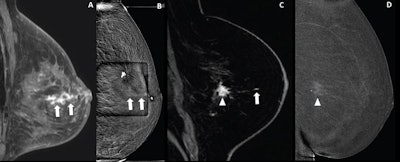

(A, B) Images depict a 65-year-old woman with prior left malignant lumpectomy. (A) Sagittal fat-suppressed contrast-enhanced T1-weighted image from diagnostic MRI performed for clear left nipple discharge shows segmental nonmass enhancement (NME) (arrows), deemed suspicious with assessment as BI-RADS category 4. The patient elected to undergo attempted contrast-enhanced mammography (CEM)-guided biopsy rather than direct MRI-guided biopsy. (B) Recombined scout image from attempted CEM-guided biopsy shows corresponding NME (arrows), serving as the biopsy target. CEM-guided biopsy was completed. Histologic assessment yielded benign findings, deemed concordant by the performing radiologist. (C,D) Images depict a 55-year-old woman with left breast invasive ductal carcinoma (IDC). (C) Sagittal fat-suppressed contrast-enhanced T1-weighted MR image from staging MRI shows known IDC (arrowhead) and additional 4-mm NME (arrow), deemed suspicious with assessment as BI-RADS category 4. Only NME was considered to represent a suspicious finding warranting biopsy. The patient elected to undergo attempted CEM-guided biopsy rather than direct MRI-guided biopsy. (D) Recombined scout image from attempted CEM-guided biopsy shows an enhancement of known IDC (arrowhead). Suspicious NME is not visualized. Given the absence of a CEM correlate to serve as biopsy target, CEM-guided biopsy was canceled. Subsequent MRI-guided biopsy of suspicious NME was completed; histologic assessment yielded IDC, deemed concordant by the performing radiologist. Image courtesy of the ARRS.

Six of the 21 women had a biopsy target identified by CEM and underwent CEM-guided biopsy; all of these were benign. The remaining 15 women lacked a CEM correlate to serve as a biopsy target and CEM-guided biopsy was canceled after CEM was continued for an average of 8.5 minutes.

These 15 women underwent MRI-guided biopsy. Of these, 13 completed the MRI-guided biopsy, which yielded the following findings: eight benign findings, two high-risk lesions, two invasive ductal carcinomas, and one ductal carcinoma in situ (DCIS). This yielded an overall malignancy rate of 27%.